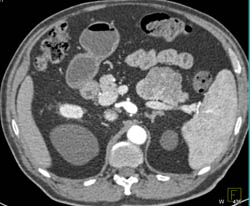

Islet Cell Tumor Occludes the Splenic Vein An Portal Vein